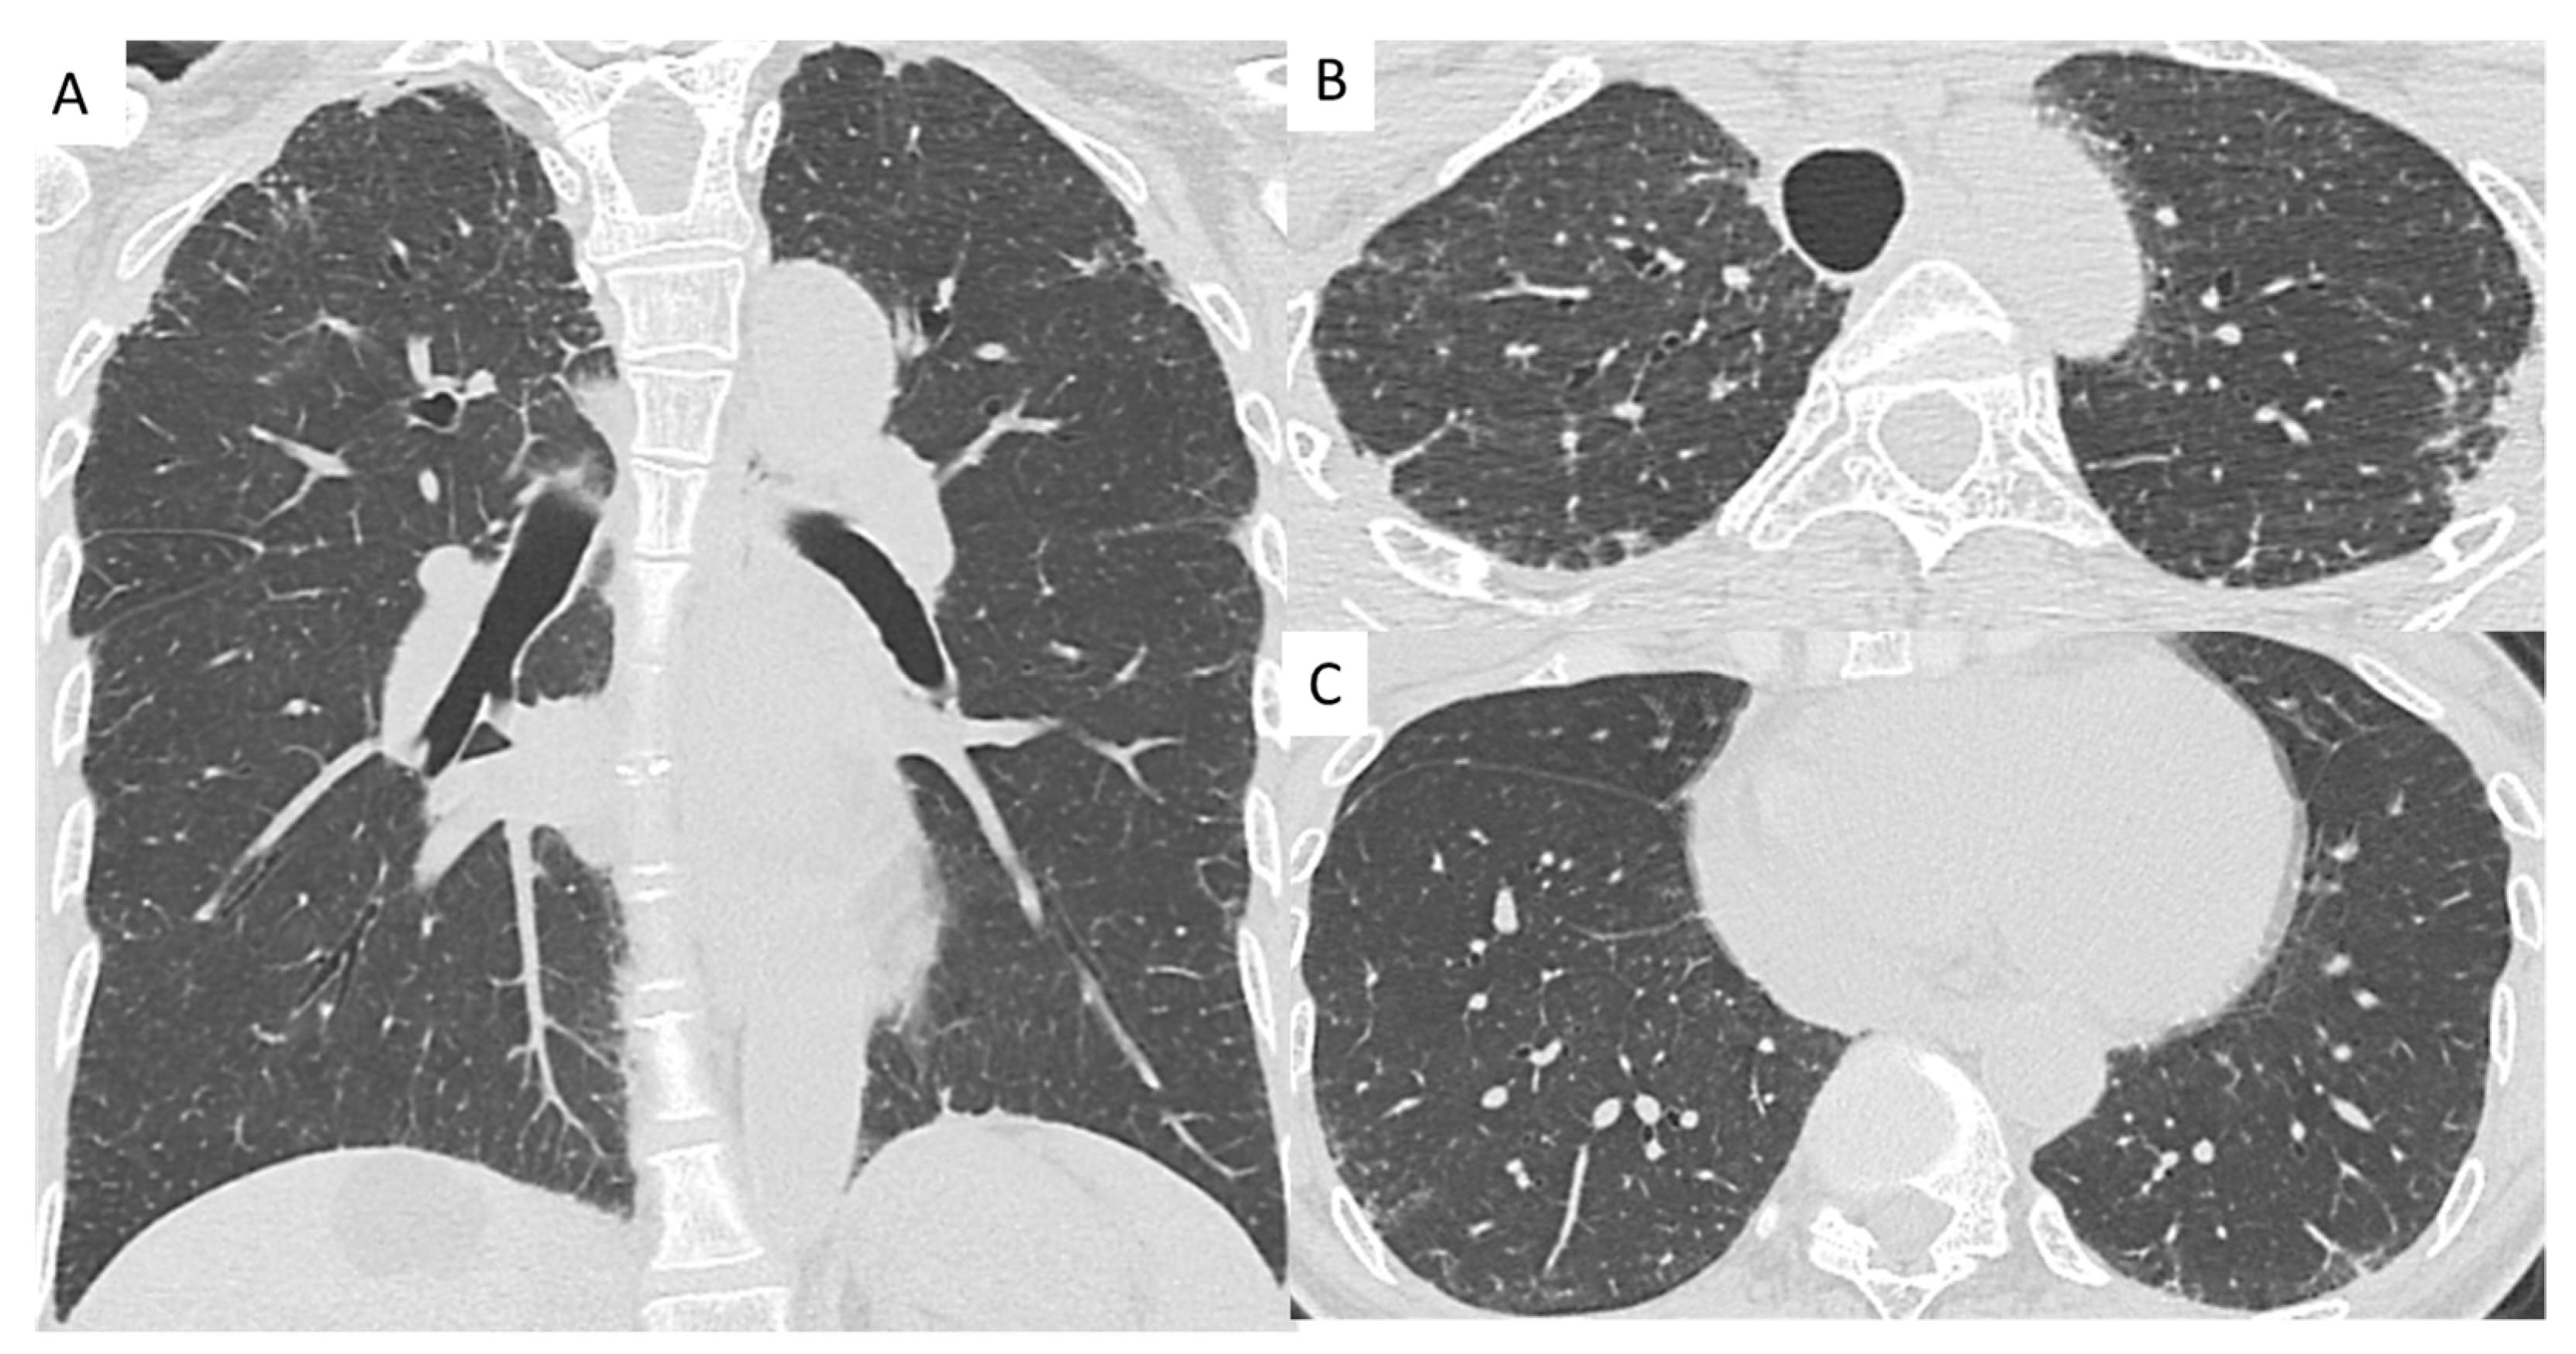

Figure 2.

Chest computed tomography images from a patient with pleuroparenchymal fibroelastosis (PPFE) with hypersensitivity pneumonitis. (A) Chest computed tomography shows bilateral dense subpleural consolidation and a loss of upper lobe volume with hilar elevation in the coronal plane. (B) There are subpleural consolidation in the upper lobes. (C) Chest computed tomography shows ground-glass opacity and reticulation in the subpleural predominance of the lower lobes.